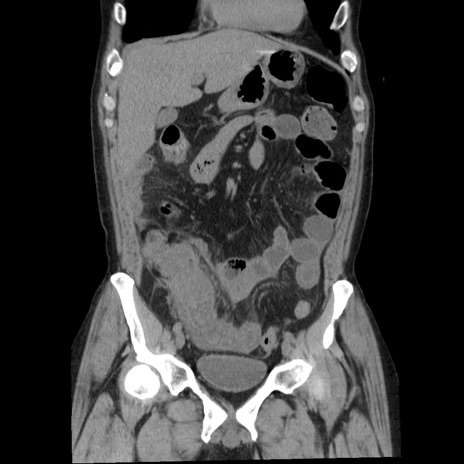

横断像

【症例】40歳代男性

【現病歴】2日前から胃痛あり。徐々に周期的な激痛に変化した。本日になっても激痛があるため受診。

【身体所見】意識清明、BT 38-39℃台あり、腹部:膨満、やや硬、右下腹部に圧痛あり。

【データ】WBC 8500、CRP 23.26